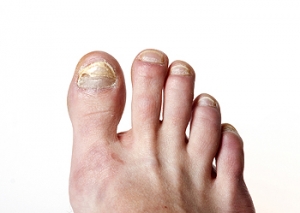

Thickened toenails that turn a yellow color can indicate that a toenail fungus has developed. Additional symptoms can include brittle nails, and in severe cases, the nail may turn black, and fall off. The fungus that causes this type of infection lives and thrives in warm and moist places, and is considered to be contagious. These can include public swimming pools, locker rooms, shower room floors, and surrounding areas. Additionally, wearing shoes and socks that are wet may significantly contribute to the onset of toenail fungus. An effective preventive technique is to wear appropriate shoes while in these areas, and it can help to wear shoes and socks that remain dry. If you have signs of a toenail fungus developing, it is suggested that you seek the counsel of a podiatrist who can offer you the right treatments for you.

Fungal infection of the toenail, or onychomycosis, typically appears as a gradual change in a toenail’s texture and color that involves brittleness and darkening.  The fungal infection itself occurs beneath the surface of the nail.  Aside from discoloration, other symptoms include the collection of debris beneath the nail plate, white marks on the nail plate, and a foul odor emanating from the nail.  If ignored, the infection can spread into other nails and the skin; in severe cases, it can hinder one’s ability to work or walk.

The toenails are particularly vulnerable to contracting infection in moist environments where people are likely to be walking barefoot, such as around swimming pools, public showers, and locker rooms.  Fungal infection may also be more likely to occur in nail beds that have been injured, and sufferers of chronic diseases such as diabetes, circulatory problems, or immunodeficiency conditions are particularly prone to developing fungal nails.

Fungal nails can be primarily prevented by practicing proper hygiene and regularly examining the feet and toes.  Carefully washing the feet with soap and water and thoroughly drying the feet afterwards are essential.  Other tips include wearing shower shoes in public areas, changing shoes and socks daily, keeping toenails clipped at a short length, wearing breathable shoes that fit properly, wearing moisture-wicking socks, and disinfecting home pedicure tools and instruments used to cut nails.

Fungal nail treatment may vary between patients and the severity of the condition.  Your podiatrist may suggest a daily routine of cleansing that spans over a period of time to ease mild infections.  Over-the-counter or prescription antifungal agents may also be prescribed, including topical and/or oral medications.  Debridement, or the removal of diseased nail matter and debris, may also be performed.  In more severe cases, surgical treatment may be needed.  In some instances, the temporary removal of the fungal nail allows for the direct application of a topical antifungal to the nail bed.  In other cases, a chronically painful fungal nail that has not responded to other treatments may be permanently removed; this allows the infection to be cured and avoids the growth of a deformed nail.